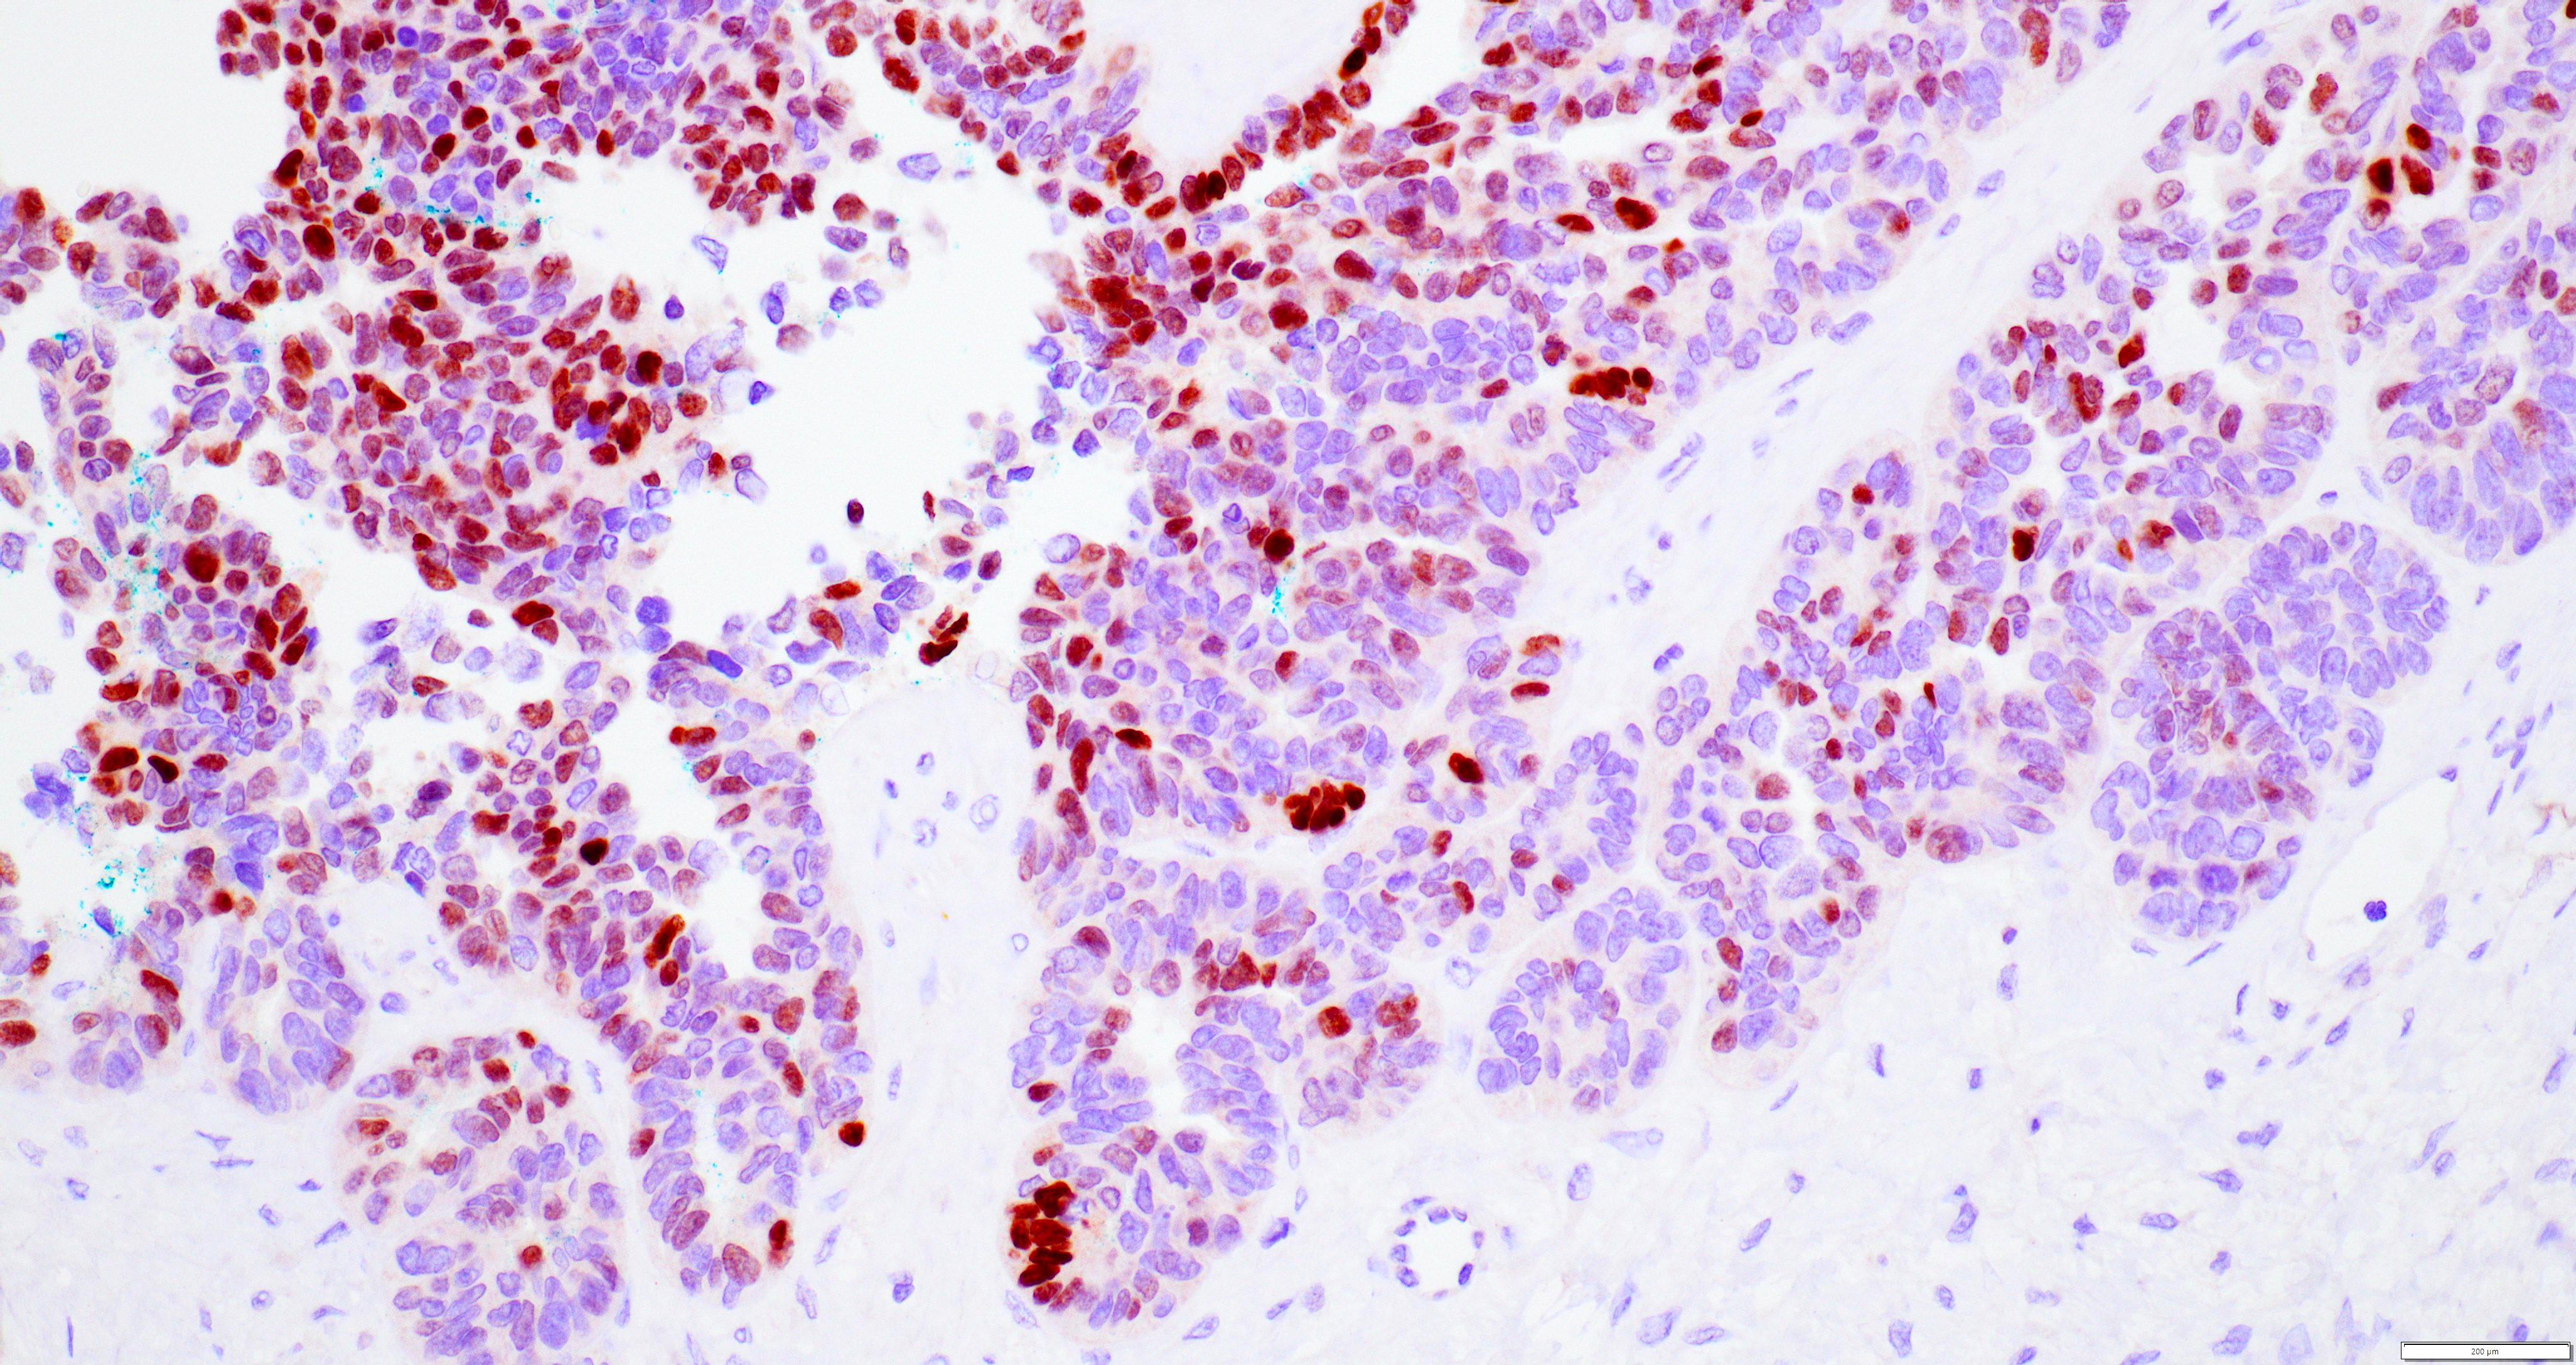

Microscopic (histologic) images

Contributed by Daniel Graham, M.D., Adele Wong, M.B., B.Ch., B.A.O. and Lucy Ma, M.D.

Positive stains

- PAX8: usually diffusely positive

- GATA3 and TTF1: focal or diffuse with inverse staining pattern described in several studies in the most recent WHO classification; cells positive for GATA3 are negative for TTF1 and vice versa (Am J Surg Pathol 2018;42:1596)

- CD10: focal and apical / luminal

- p53 wild type

- MMR proficient